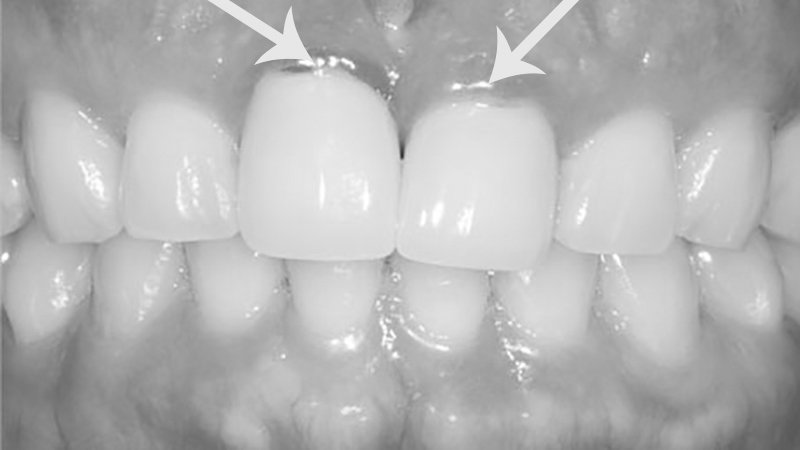

• pigmentação gengival

O metal presente na subestrutura de próteses fixas com porcelana pode, com o passar dos anos, corroer e provocar pigmentos ou manchas escuras nas gengivas. E, infelizmente, a pigmentação gengival por metal, além de comum, também pode ser causada pelo metal presente em restaurações com amálgama de prata. Quando essas pigmentações aparecem em dentes na região anterior da arcada, os danos estéticos podem ser desastrosos e necessitar de cirurgias plásticas gengivais para a correção do problema.

Casos mais avançados de inflamação associada à alergia ao metal de próteses dentárias apresentam áreas com extensa retração gengival Nesses casos, principalmente quando a retração está em região anterior e estética, pode ser necessário um procedimento periodontal estético para recobrir as áreas de exposição das raízes dentárias envolvidas.